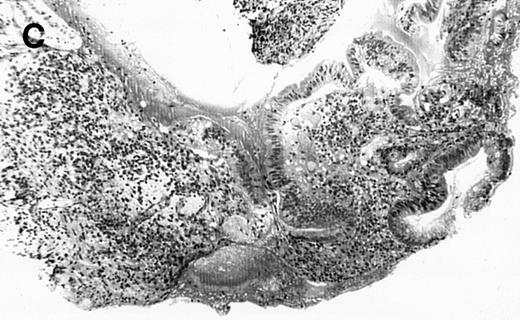

(A) Case no. 1. (B and C) Case no. 2. (D) Case no. 3. (E) Case no. 4. (A, B, D, and E) Duodenal biopsies showing total villous atrophy with crypt hyperplasia and infiltration of lamina propria by nonatypical inflammatory cells (Hematoxylinandeosin; original magnification × 10). (C) Jejunal biopsy showing villous atrophy and ulcerations with regenerative epithelial changes on the border of ulcerations; no evidence of lymphoma.

The 4 patients with complicated CD had duodenal biopsies consistent with untreated CD; total villous atrophy, intraepithelial lymphocytosis, crypt hypertrophy, and inflammation of lamina propria with benign-appearing lymphocytes, plasma cells, and eosinophils were observed. There was no histological evidence of lymphoma. Patient no. 4 also had biopsies performed at the border of duodenal ulcerations that showed epithelial erosions without histological evidence of lymphoma.